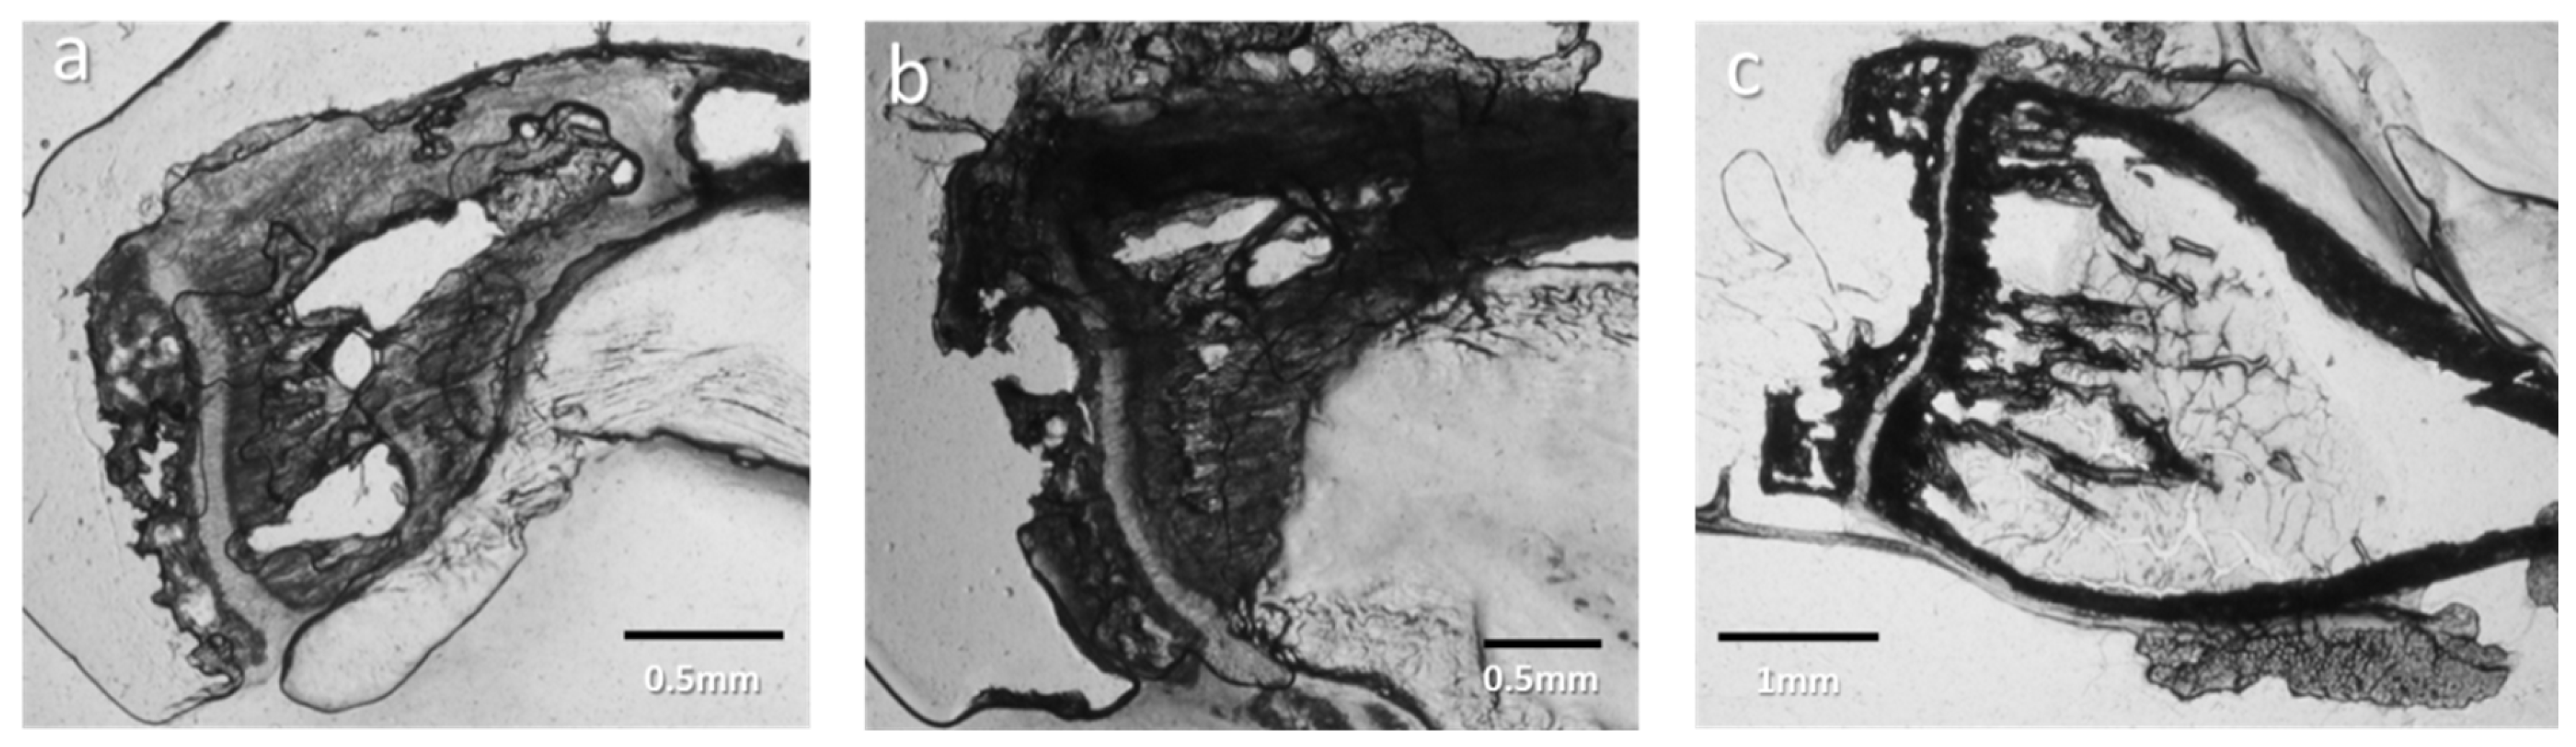

3.1.6. Cell Identification by Microscopies of Overproduced Bone-like Materials

3.2. Topology at Late Stage of Osteosarcoma Development